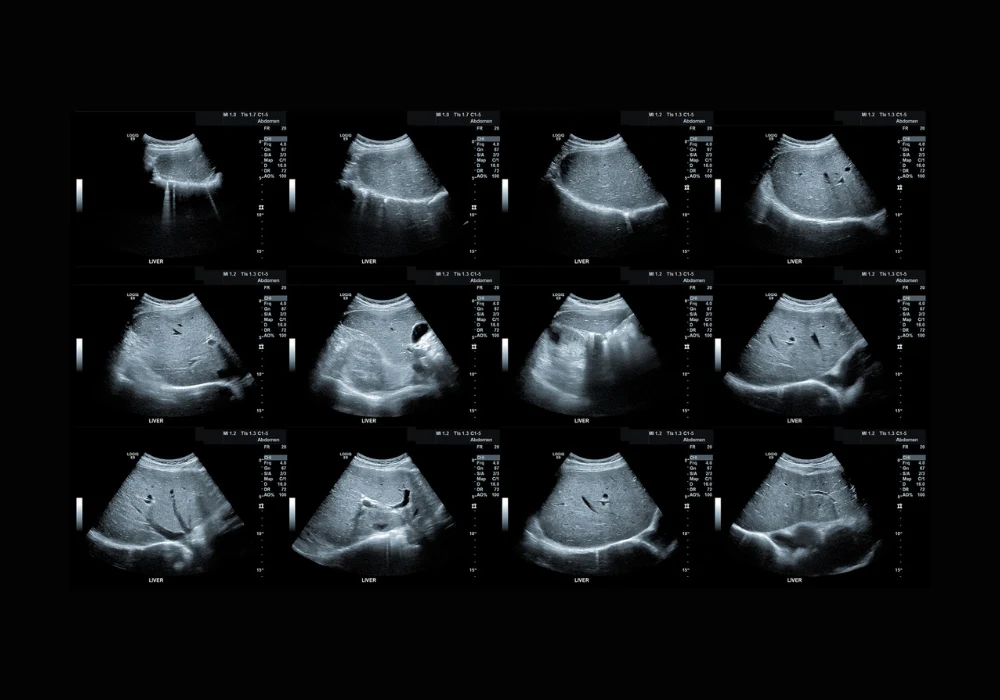

Tissue attenuation imaging (TAI), tissue scatter-distribution imaging (TSI) and two-dimensional shear-wave elastography (SWE) have emerged as promising tools for evaluating hepatic steatosis, inflammation and fibrosis. TAI quantifies the attenuation of ultrasound signals in liver tissue, while TSI evaluates the distribution of backscattered signals. SWE assesses liver stiffness by measuring shear-wave propagation. These methods were applied across a cohort of 114 adult participants recruited from four centres in China and Korea, all scheduled for liver biopsy due to suspected MASH, abnormal liver function or liver donor evaluation.

Among the participants, 67% were diagnosed with MASH and 34% were identified as having high-risk MASH, defined by fibrosis stage F2 or higher. Multivariable analysis showed that TAI and TSI were independently associated with hepatic steatosis, while SWE was associated with fibrosis. TAI and TSI values increased with advancing steatosis grade. TAI achieved area under the curve (AUC) values of 0.90, 0.93 and 0.78 for detecting steatosis grades S1 or higher, S2 or higher and S3, respectively. TSI demonstrated similar performance with AUC values of 0.94, 0.89 and 0.80 across the same thresholds. These results confirm the utility of both techniques in accurately grading hepatic fat content, especially in early and moderate stages.